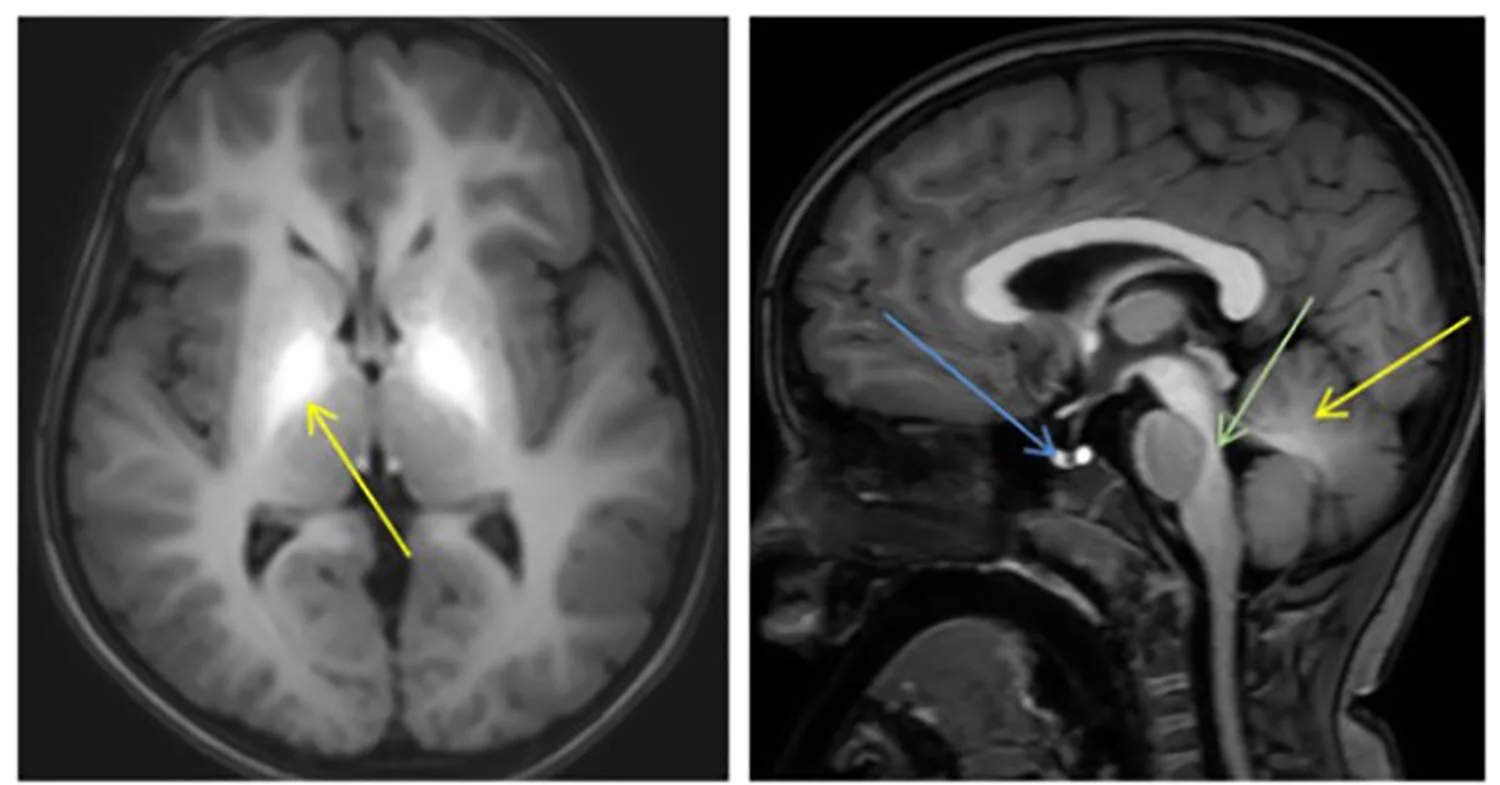

Manganese is an essential trace metal and critical for brain physiology and development. However, excess manganese is neurotoxic leading to dystonia-parkinsonism, psychiatric and intellectual disability.

Our research has identified two manganese transporter defects associated with manganese neurotoxicity – hypermanganesaemia with dystonia 1 (HMNDYT1) and 2 (HMNDYT2). They are caused by loss-of-function mutations in SLC30A10 and SLC39A14, respectively, that encode manganese transporters that act in conjunction to mediate metal excretion. Manganese deposition in the brain leads to progressive, childhood-onset dystonia-parkinsonism associated with significant disability and premature death.

MRI brain